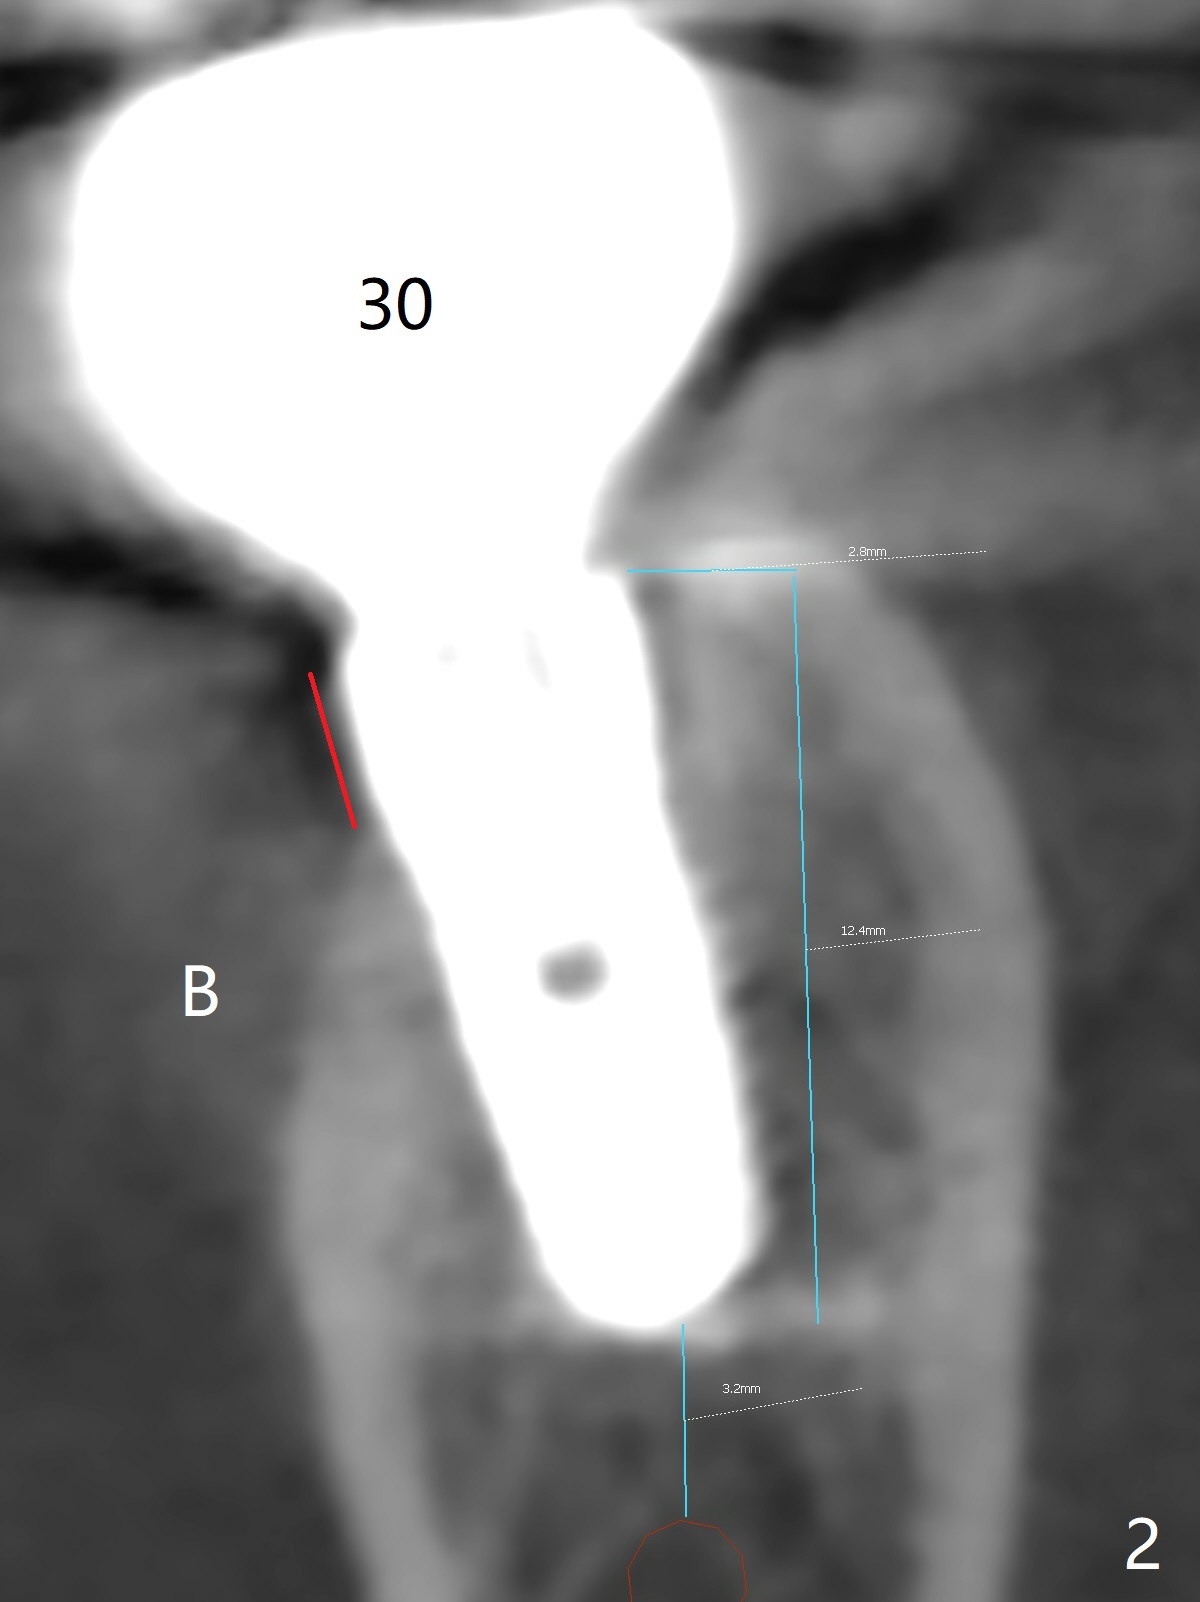

Twenty six months post cementation, periimplantitis develops buccally at #30 (Fig.1) due to buccal (B) placement (Fig.2) with buccal thread exposure (red line), as compared to the same sized implant at #19 (Fig.3). After removal of the crown and abutment and incision, use Titanium brush to clean the exposed threads. Following implant removal and removal of the lingual bone, place the same implant lingually (Fig.4 arrow) with the used-to-be-exposed surface facing lingual (Fig.4 red line). The buccal gap will be filled with autogenous bone harvested lingually and allograft. Use 2-3 pieces of PRF membranes to close the wound, i.e., to bury the implant. A 5x13 mm implant (Fig.5) placed lingually (Fig.6 L) appears to be unable to gain more than .77 mm native bone (Fig.7). Lab declines to make a guide.